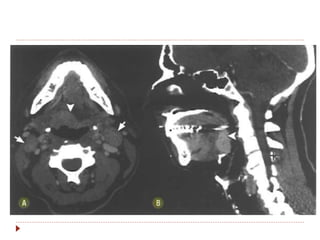

Hipofaringe  Do ossohioide ao esôfago cervical.  Três áreas de interesse:  Seio piriforme (65%).  Região pós-cricoide  Parede posterior  Os linfáticos drenam para cadeia jugular e cruzam para o lado contralateral (II, III, V e retrofaríngeos).  Sintomas: disfagia, rouquidão, dispneia.  Patologia: CEC.

 Três áreas de interesse:

 Seio piriforme (65%).

 Região pós-cricoide

 Parede posterior

 Os linfáticos drenam para cadeia

jugular e cruzam para o lado

contralateral (II, III, V e

retrofaríngeos).

 Sintomas: disfagia, rouquidão,

dispneia.

 Patologia: CEC.